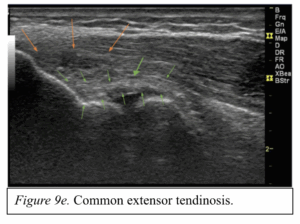

A focussed hand specific clinic assessment (table 4) can help to rule in or out complete ruptures but is less sensitive for (partial tears). Where a closed tendon rupture is suspected and the clinical exam is uncertain, imaging can help to confirm a diagnosis. MRI is the gold standard imaging for closed tendon injuries and has good sensitivity, but US is generally preferred as it allows the benefit of dynamic assessment of tendons, locating retracted tendon ends and more chronic conditions, such as tendinopathy or tendinosis (Figure 1-2).

Figure 9. Ultrasound images of various tendinous pathologies.